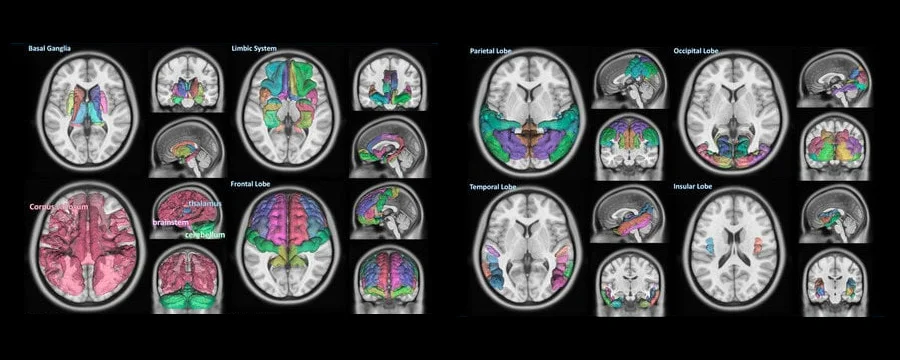

검은색 배경에 표시된 뇌 영상 분석 결과 화면

클라우드 기반 자동 분석 플랫폼 구축을 통한 뇌 영상 분석